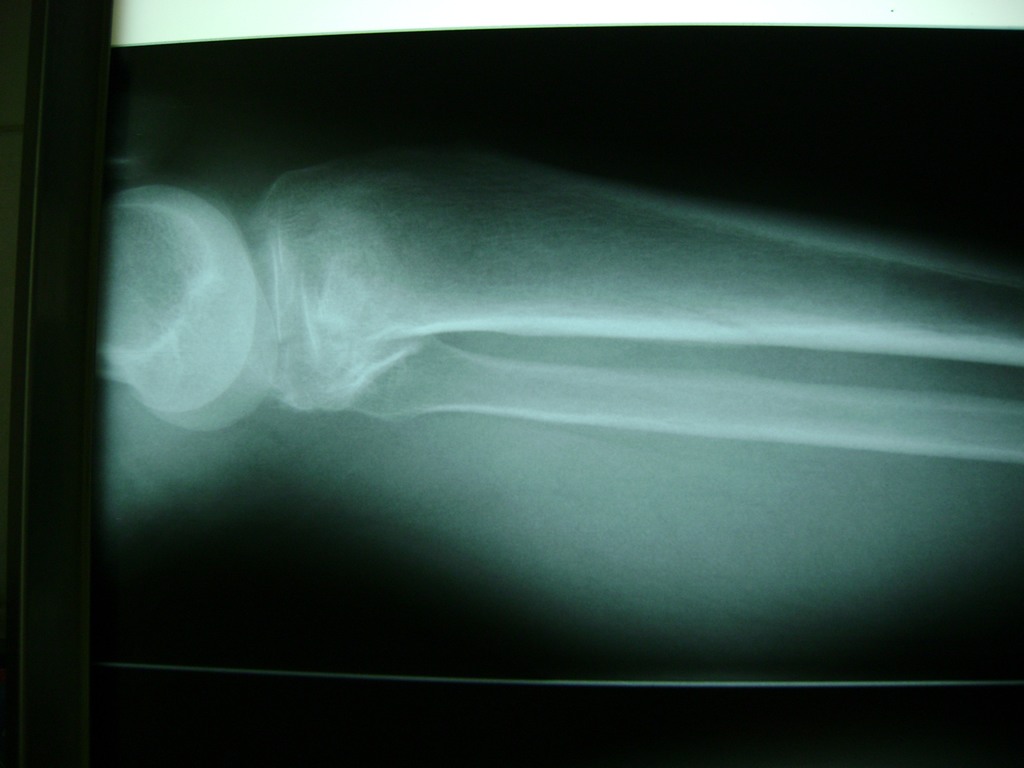

La artroscopia de rodilla es un cirugía en el cual la estructura interna de la articulación es examinada ya sea para realizar un diagnostico o para realizar un tratamiento, este procedimiento se realiza utilizando un instrumento parecido a un pequeño tubo llamado artroscopio.